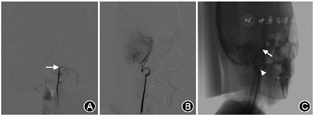

临床资料 患者男性,25岁。因突发头晕、头痛5 d于2019年9月29日就诊。患者无明显诱因突发头晕,右侧转颈时加重,伴有明显的视物旋转感,恢复中立位时头晕可缓解。2 d前曾在外院就诊,头部MRI、MRA示双侧小脑多发梗死,右侧病灶范围较大;MRA提示右侧椎动脉未显影,双侧大脑后动脉均发自同侧颈内动脉,左侧大脑前动脉A1段未显示(右侧共干)。既往无高血压、糖尿病、脑血管病、心脏病病史;否认风湿及自身免疫性疾病史,平时无颈部疾病及按摩史,病前无颈部疼痛、外伤、手术、放化疗病史;吸烟5年(2~3支/d),机会饮酒。否认家族遗传史及类似疾病病史。入院诊断:青年不明原因卒中待查。入院后体格检查:生命体征及血压正常,心肺检查未见异常;颈部和眶内无杂音。神经系统体检:脑神经正常,四肢肌力Ⅴ级、肌张力正常, 四肢腱反射适中, 双侧巴宾斯基征(-);深浅感觉及共济检查未见异常。患者身高175 cm、体重75 kg。住院期间患者多次于转颈时反复出现头晕、头痛明显加重,但发作时未见确切的神经系统定位体征,恢复中立位后症状迅速缓解。辅助检查:血常规、生化全项及甲状腺功能、糖化血红蛋白、凝血四项、自身免疫抗体、肿瘤标志物均未见异常,但血浆同型半胱氨酸明显升高[45.96(正常值:3.70~13.90)μmol/L]及类风湿因子水平升高[31.2(正常值:0~20.0)U/ml]。入院后进一步行心电图及经胸心脏超声、对比增强经颅多普勒超声(发泡,仰卧位)检查均未见异常(2019年9月29日)。进一步行颈部血管彩色多普勒超声(CDU)检查(2019年9月29日,图1A~E),结果仍提示右侧椎动脉节段性闭塞;向右侧转颈至近90° 过程中,左侧椎动脉V2段血流速度及频谱形态从正常迅速变为舒张末期血流信号消失的“低流速高阻力”频谱形态,同时寰枢椎段管腔受压变窄,狭窄以远呈缺血改变,恢复中立位后椎动脉血流速度及频谱形态也恢复正常。为明确寰枢椎段椎动脉管腔受压变窄的原因,行颈段MRI检查(2019年9月29日;图2A、 B),提示可疑寰枕关节融合、寰枢关节脱位及枕骨大孔狭窄。进一步经右侧股总动脉穿刺行全脑数字减影血管造影(DSA),获取3D DSA(图3)图像的同时获得C臂CT (Dyna-CT,图4)图像信息,结果DSA可见 V1~2段断续显影,于C1~2水平闭塞,颅内段椎动脉未见显影,提示右侧椎动脉夹层可能性大(图3A),颈部中立位时左侧椎动脉管腔通畅并汇入基底动脉(图3B);令患者向右侧转颈45~90°过程中,患者头晕再次加重,同时显示左侧椎动脉在C1~2水平明显受压、管腔变窄(图3C),左侧椎动脉颅内段显影浅淡,基底动脉部分显影至消失(图3C)。根据患者上述旋转性头晕发作病史,结合颈部血管CDU及DSA于头颈部旋转后出现椎动脉特殊的血流动力学变化特点,临床诊断考虑为BHS并颅内段椎动脉夹层所致的双侧小脑梗死可能性大。住院期间给予患者阿司匹林及氯吡格雷双联抗血小板、限制颈部转动以及佩戴颈托等保守治疗,同时根据外科会诊建议(行手术治疗解除血管受压),向患者交代病情。但患者要求药物保守治疗,拒绝手术。2周后患者头晕症状基本好转出院。出院时嘱患者避免颈部剧烈旋转动作。出院后1个月随访,患者病情基本稳定,偶发头晕。

DSA仍是目前诊断BHS的“金标准”。本例患者DSA也进一步证实左侧椎动脉呈间歇性开放,结合颈动脉超声出现的旋转后椎动脉特殊血流动力学变化,可以明确诊断BHS。DSA同时可见左侧椎动脉为优势动脉,双侧大脑后动脉均发自同侧颈内动脉,考虑该患者存在颅内动脉先天发育异常或变异的可能性大,包括颅内段右侧椎动脉夹层也不除外为先天变异的可能。颈动脉超声可见右侧椎动脉纤细,提示患者存在右侧椎动脉发育不全。目前对颅内动脉夹层的病理生理学知之甚少。在正常人群中椎动脉发育不全并不罕见,这可能与后循环缺血梗死有关。有学者认为椎动脉发育不良(vertebral artery hypoplasia)可增加同侧椎动脉自发性夹层发生的风险[22]。本例患者发生双侧小脑梗死的机制,推测与BHS并右侧椎动脉夹层闭塞,致反复发生间歇性左椎动脉严重缺血,以及存在的大脑后动脉变异致前后循环供血被打乱有关[23]。Hong等[23]的研究结果显示,胚胎型大脑后动脉(fetal-type posterior circle of Willis, FTP)会显著降低后循环的血流灌注。Lochner等[24]对13例后循环缺血患者的研究结果显示,FTP最常见的是双侧变异,并全都伴有椎基底动脉发育不良,其中4例患者为脑干或小脑梗死,9例为后循环短暂性脑缺血发作(transient ischemic attack),提示FTP与后循环缺血有关。关于椎动脉夹层的发生,高分辨MRI (HR-MRI)能清晰显示动脉夹层的血管壁改变,可能对动脉夹层形成的病理生理学机制提供帮助。对本例患者未进一步行HR-MRI检查,有待今后在进一步随诊中予以完善。

关于BHS的发病机制,一项长达8年时间收集的21个病例的研究结果显示,12例为向优势椎动脉对侧转颈时优势椎动脉于C1~2水平受压发生旋转性椎动脉闭塞,其余包括同侧转颈、双侧转颈、V1~4水平优势椎动脉受压等情况,其中以对侧转颈C1~2水平受压为主要发病原因[25],国内先前亦有报道患者右侧椎动脉V3段(颈C1~2水平)狭窄机制与长期肩扛搬运、牵拉及慢性劳损等引起颈椎骨质增生、韧带纤维化以及局部软组织压迫有关,左侧转颈时右侧椎动脉进一步受压变窄导致后循环缺血加重[26]。本例患者颈段MRI显示寰枕关节融合、寰枢关节脱位,Dyna-CT融合图像证实寰枢椎异常致左侧椎动脉明显受压,这也是本患者在右侧椎动脉先天发育不全、大脑后动脉存在变异及存在颅内段椎动脉夹层基础上,发生双侧椎动脉缺血的重要原因之一。患者寰枕关节融合、寰枢关节脱位的原因不除外与先天异常有关[27, 28],但本例患者血液化验风湿指标及同型半胱氨酸明显增高,不除外风湿性疾病所致的寰枕关节融合、寰枢关节脱位的可能,虽然患者目前无关节疼痛、变形等异常表现[29, 30]。寰枢关节脱位、枕骨大孔变窄致反复摩擦挤压,以至该侧椎动脉产生夹层闭塞也可能是本患者右侧椎动脉夹层闭塞的原因。有学者认为BHS的病理机制与寰枢关节处椎动脉受压出现内膜撕裂、壁内血肿,甚至假性动脉瘤等夹层有关,继而导致血栓形成或栓塞。本例患者目前仍在进一步随访中,目前无明显发作性眩晕表现。